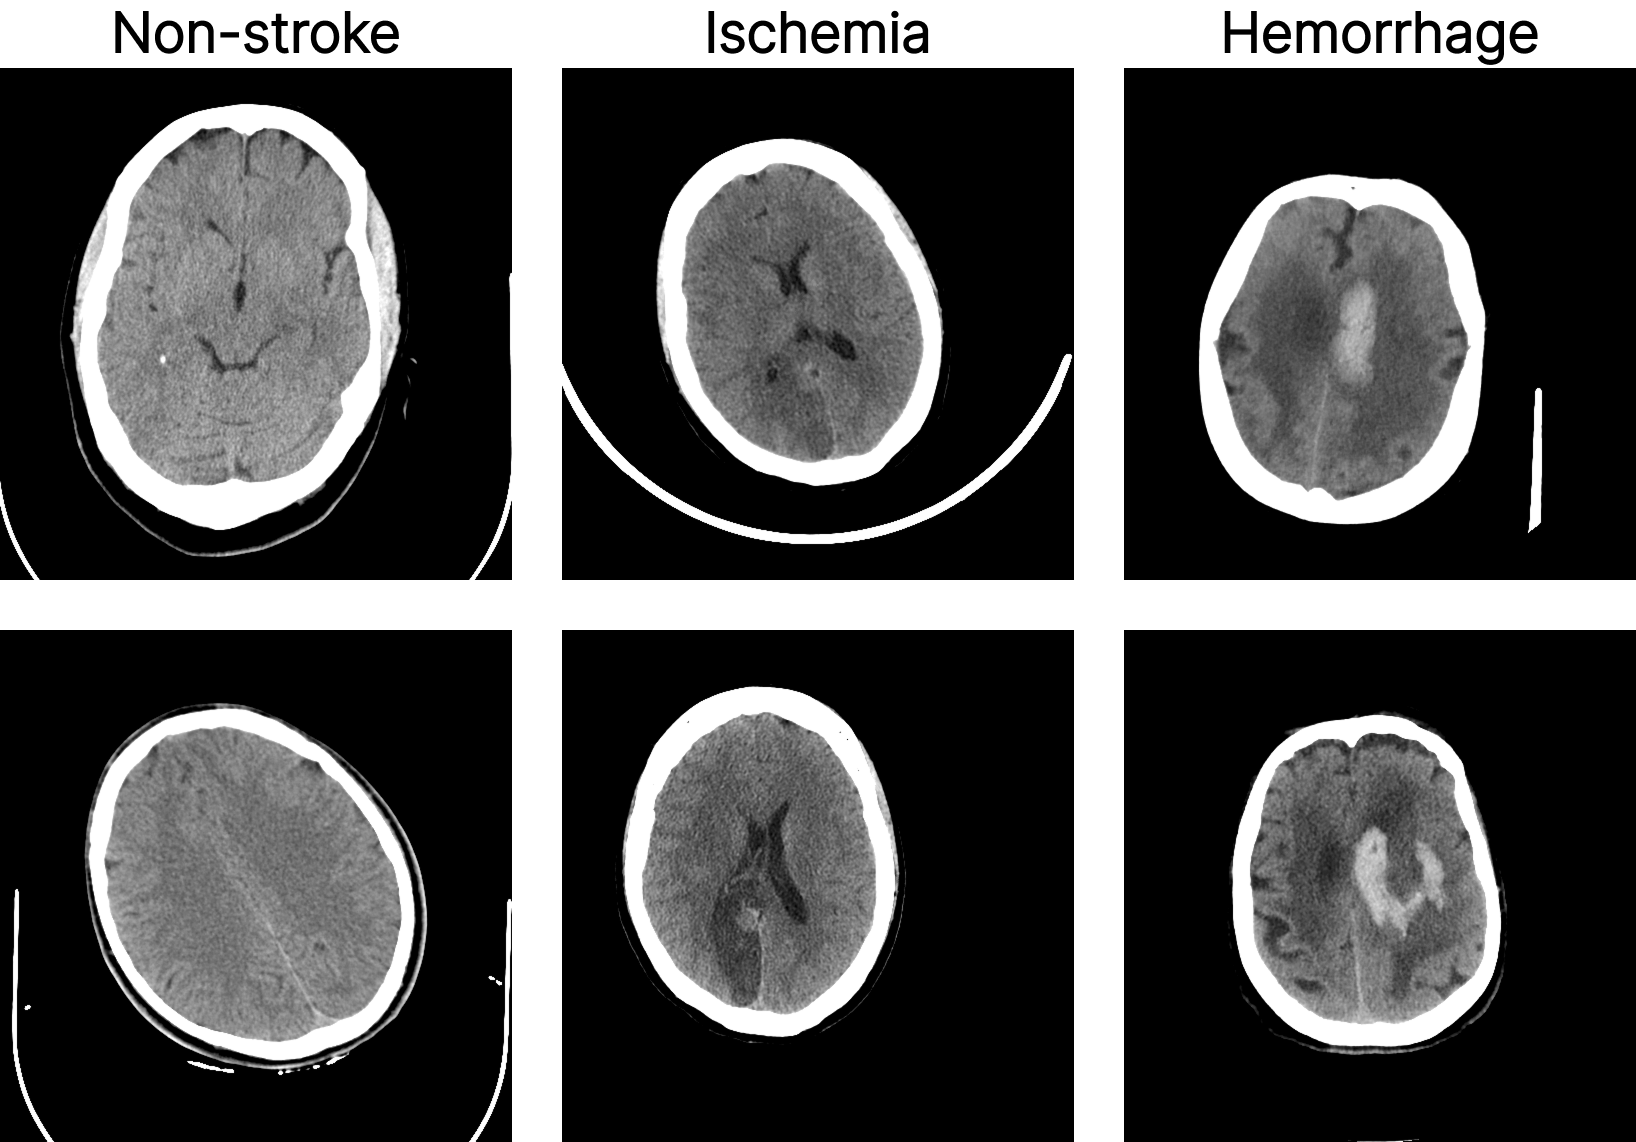

We use the Stroke Dataset released as part of the Artificial Intelligence in Healthcare Competition (TEKNOFEST 2021) [15]. It consists of 6,774 brain CT cross-sectional images in PNG format, annotated and curated by a team of seven radiologists. The dataset is divided into three classes: 4,551 non-stroke, 1,093 hemorrhagic stroke, and 1,130 ischemic stroke cases. The dataset is publicly available, and representative samples are shown in Fig. 2.

Refer to caption

Figure 2: Sample images from the used dataset in this work.

To structure the experiments, the dataset was reorganized into two settings. The first addresses stroke detection by grouping ischemic and hemorrhagic cases into a single positive class and using non-stroke samples as negatives. The second focuses on stroke subtype classification, considering only ischemic and hemorrhagic cases and excluding non-stroke images. In both settings, the data were randomly split into training, validation, and test sets following an 80-10-10 ratio. Data augmentation was used, including random horizontal flips, rotations up to 10°, and brightness, contrast, and saturation jittering. Images were resized to 224×\times224 and normalized using standard ImageNet statistics.